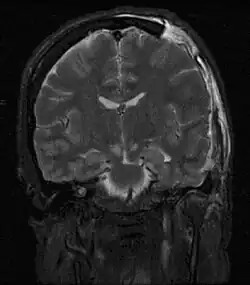

MRI showing injury due to brain herniation | |

Brain herniation is a potentially deadly side effect of very high pressure within the skull that occurs when a part of the brain is squeezed across structures within the skull. The brain can shift across such structures as the falx cerebri, the tentorium cerebelli, and even through the foramen magnum (the hole in the base of the skull through which the spinal cord connects with the brain). Herniation can be caused by a number of factors that cause a mass effect and increase intracranial pressure (ICP): these include traumatic brain injury, intracranial hemorrhage, or brain tumor.[1]

Treatment involves removal of the etiologic mass and decompressive craniectomy. Brain herniation can cause severe disability or death. In fact, when herniation is visible on a CT scan, the prognosis for a meaningful recovery of neurological function is poor.[2] The patient may become paralyzed on the same side as the lesion causing the pressure, or damage to parts of the brain caused by herniation may cause paralysis on the side opposite the lesion.[11] Damage to the midbrain, which contains the reticular activating network which regulates consciousness, will result in coma.[11] Damage to the cardio-respiratory centers in the medulla oblongata will cause respiratory arrest and (secondarily) cardiac arrest.[11] Investigation is underway regarding the use of neuroprotective agents during the prolonged post-traumatic period of brain hypersensitivity associated with the syndrome.[17]